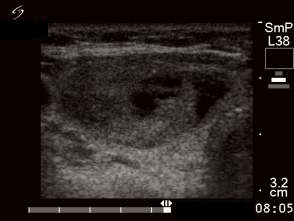

First session of the sclerotherapy (second row of images):

Clinical presentation: the patient had no complaints.

Hormonal investigation indicated subclinical hyperthyroidism (TSH 0.02 mIU/L, FT4 17.4 pM/L).

Ultrasonography: the nodule in the right lobe significantly increased.

Suggestion: definitive therapy. The patient chose ethanol sclerotherapy.

Five sessions of ethanol was administered. We gave 13 mL ethanol in all.